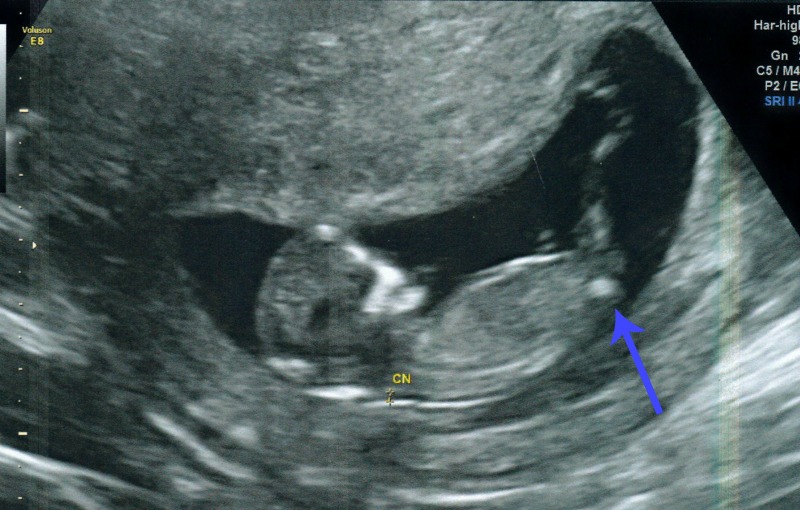

However, I would still love some guesses.... based on nub, skull, any other random theory or just feeling! This is just for fun and I will have a chance to find out in 4 weeks at my next scan (but undecided whether to or not!).

Please guess away ladies - I have put an arrow where I personally think you can see a nub peeping out just based on what I remember from the scan video.